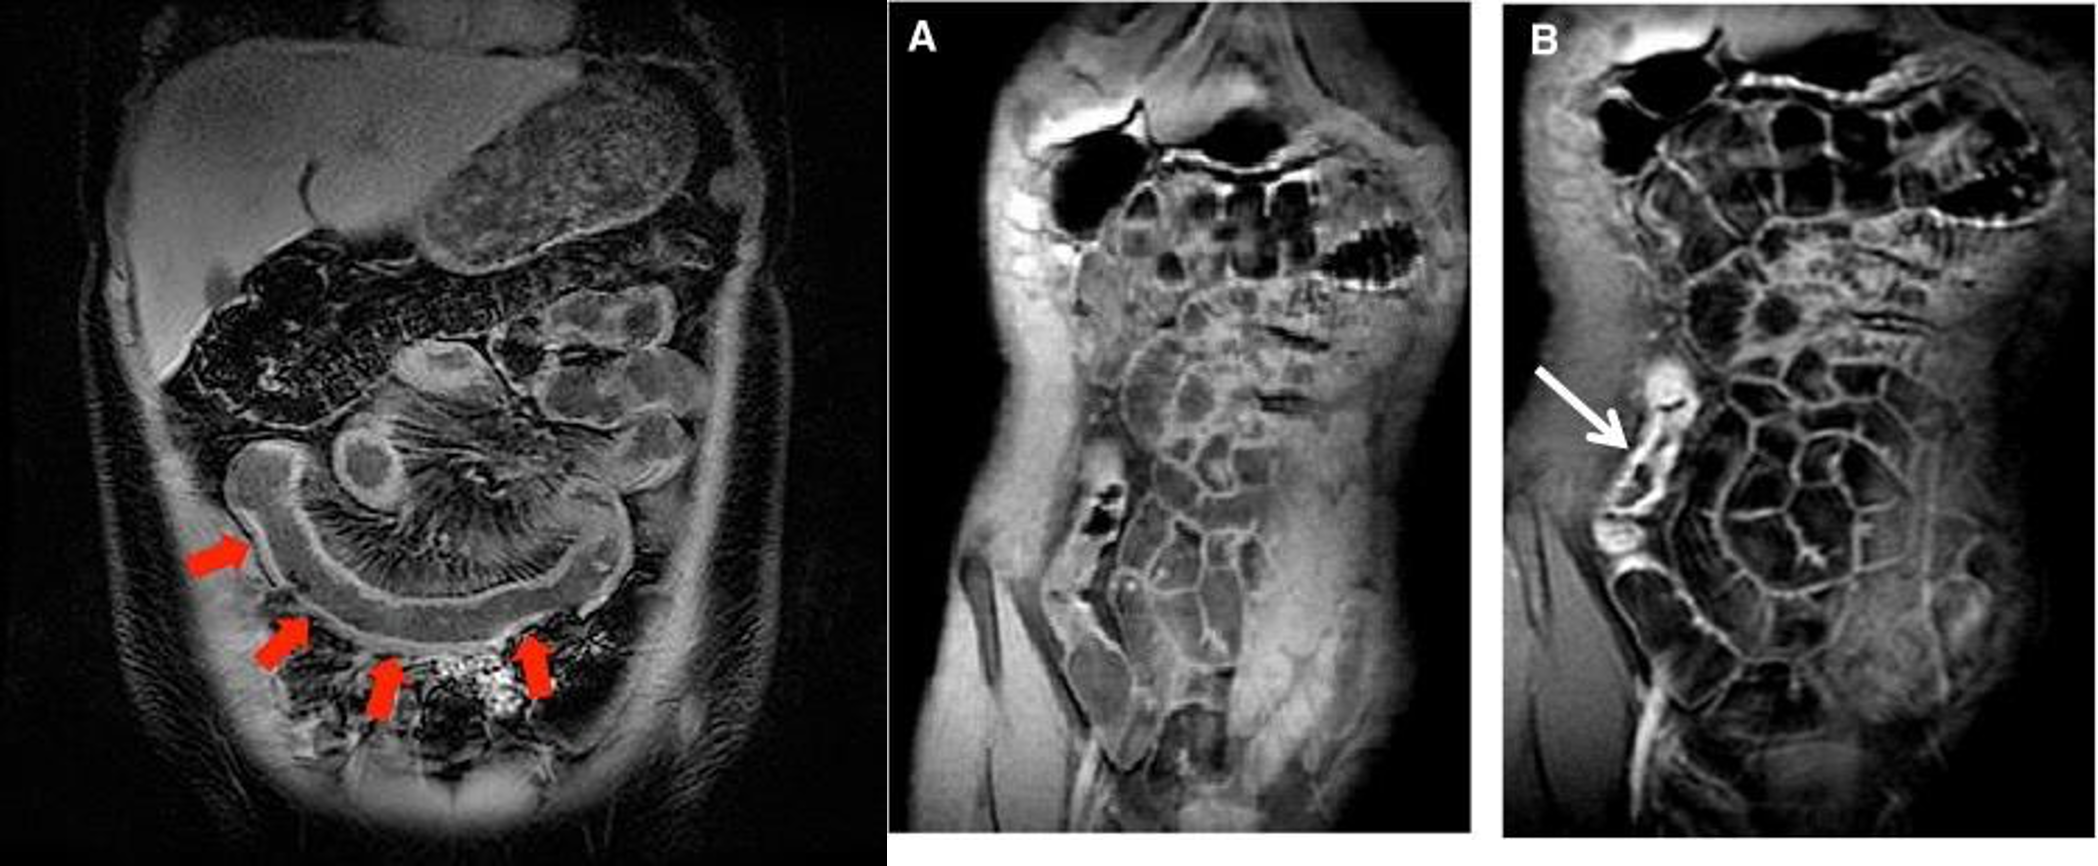

- & 2 MRE -

- MRE (crohn)

- MRE